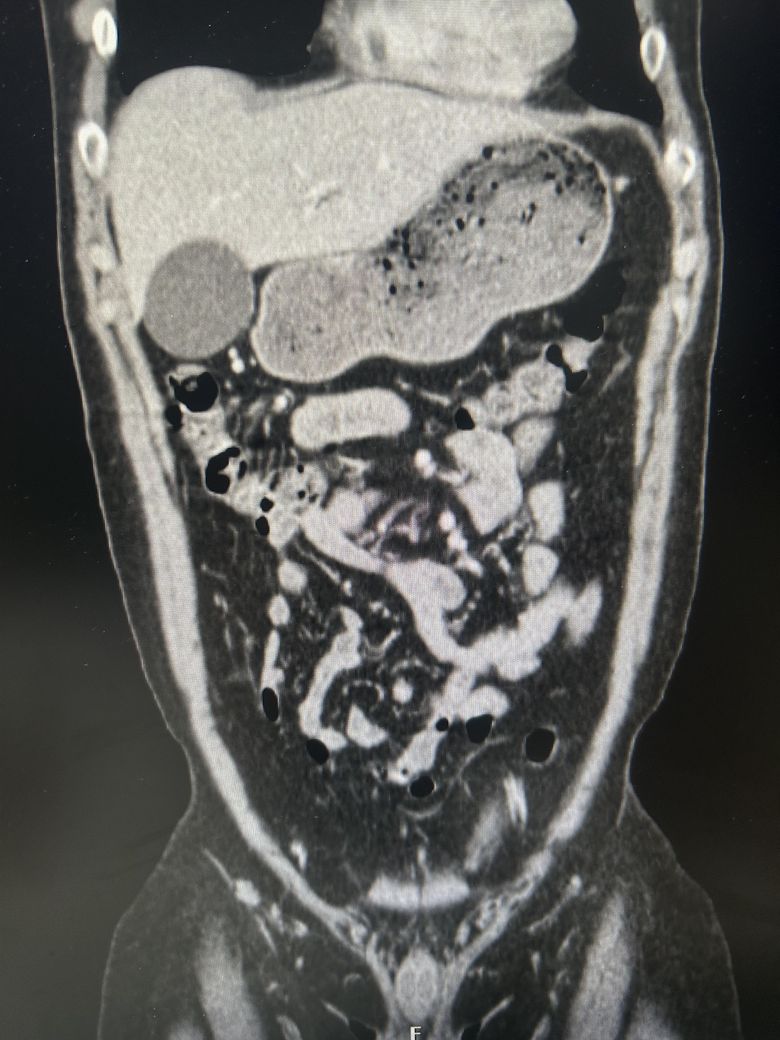

우상복부 통증(좌상복부 통증도 생김), 오른쪽 어깨에서 허리까지통증, 소화불량, 팽만감,답답함, 설사 증상이 있는데..... 담낭염이 맞을까요?

• 2번 째 사진

CT에서 담낭염은 담낭벽이 두꺼워보이고 벽이 조영증강되는데

환자분 자료의 경우 그런 소견이 뚜렷하게 보이지는 않는 것 같습니다.

• 애매합니다. 담낭의 크기가 다소 늘어나 보이긴 합니다만, 당남염을 강력하게 의심할만한 다른 소견들이 보이지는 않습니다. 가령 담낭의 벽이 두꺼워지거나 담낭 주변의 염증 소견, 담낭 목을 막고 있는 담석 등이 따로 관찰되거나 하지는 않기 때문에 담낭염을 강력하게 의심하기는 어려워 보입니다. 우상복부의 압통 및 머피징후 등의 신체검진 소견이 있다면 담낭염의 가능성을 고려해볼 수 있겠습니다만, 해당 CT 소견만으로는 판단하기 어렵습니다.

첨부해주신 CT 영상에는 담낭 주변에 두드러지는 염증소견이 관찰되지 않습니다. 다만 영상의 모든 단면을 확인한 것이 아니라서 담석증의 여부에 대해서는 확답드릴 수 없습니다. 증상이 지속되면 내과에서 진료를 받아보시는 것을 권해드립니다.